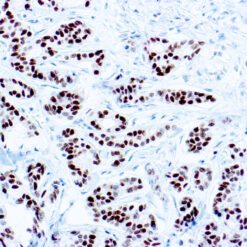

NUT1

NUTM1 is a Protein coding gene. Diseases associated with NUTM1 include NUT Midline Carcinoma and Spindle cell Carcinoma. The molecular weight of this antigen is 120kDa. Among its related pathways are Chromatin regulation/ Acetylation. An important paralog of this gene is NUTM2G. Plays a role in the regulation of proliferation. Regulates TERT expression by modulating SP1 binding to TERT promoter binding sites.

| Cellular Localization | Cytoplasmic, Nuclear |

| Positive Control Tissue | Testis |